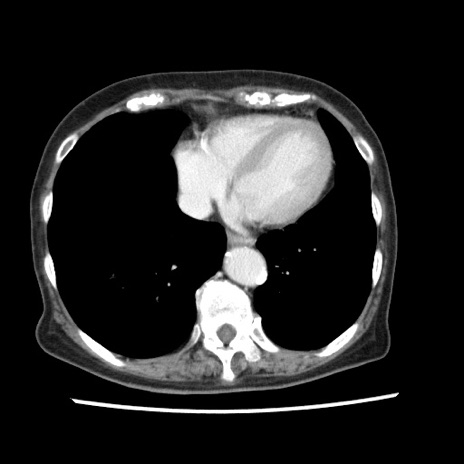

症例1(横断像)

症例

【症例】80歳代女性

【主訴】腹痛

【現病歴】8時間前から腹痛あり来院。

【既往歴】糖尿病、脂質異常症、子宮体癌にて子宮全摘術

【身体所見】意識清明・会話良好だが腹痛で苦悶様、全腹部にわたって反跳痛と圧痛あり

【データ】WBC 13600、CRP 0.14、LDH 224、CK 90